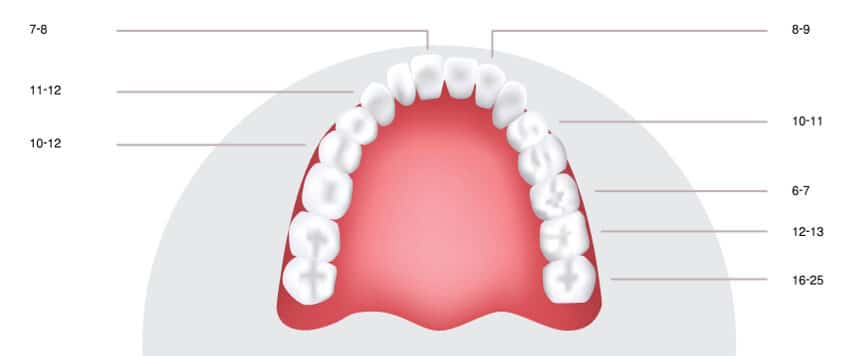

Die jeweils letzten Backenzähne (Molaren) am Ende der Zahnreihen von Ober- und Unterkiefer werden Weisheitszähne genannt. Man nennt sie so, weil sie meist erst zwischen dem 16. und 25. Lebensjahr aus Kieferknochen und Weichgewebe durchbrechen. Häufig kommen bei einem Erwachsenen vier Weisheitszähne vor, doch können es auch weniger sein. Manchmal finden die Weisheitszähne nur teilweise oder gar nicht an die Oberfläche, was zu verschiedenen Problemen führen kann.

Weisheitszähne sind die jeweils letzten Backenzähne am Ende der Zahnreihen von Ober- und Unterkiefer, die meist erst zwischen dem 16. und 25. Lebensjahr aus Kieferknochen und Weichgewebe durchbrechen und aufgrund ihrer Größe oft Probleme bereiten.

Normalweise verfügt ein Mensch über insgesamt 32 Zähne. Dazu gehören bei den meisten Menschen vier Weisheitszähne – je einer in jedem Gebissquadranten. Es gibt aber auch Menschen, die weniger oder gar keine Weisheitszähne entwickeln. Die Gründe sind ein komplexes Zusammenspiel aus individuellen genetischen und evolutionären Faktoren, die letztlich darüber entscheiden, wie viele Weisheitszähne ausgebildet werden.

Mit fortschreitender Evolution und sich verändernden Ernährungsgewohnheiten hin zu gekochter, weicherer Nahrung bildeten sich das Volumen des Kiefers immer weiter zurück. Die eigentlich überflüssig gewordenen Weisheitszähne hielten mit dieser Entwicklung allerdings und sind deshalb heute noch bei vielen Menschen angelegt. Da Weisheitszähne meist erst zwischen dem 16. und 25. Lebensjahr durchbrechen, müssen sie sich in eine meist schon vollständige Zahnreihe eingliedern, ohne immer den ausreichenden Platz hierfür zu haben. Infolgedessen können sich Schmerzen, Entzündungen oder Zahnfehlstellungen entwickeln.

Das optimale Alter für die Entfernung von Weisheitszähnen liegt zwischen 16 und 25.* In dieser Lebensphase sind die Wurzeln der Weisheitszähne oftmals noch nicht vollständig ausgebildet, der Kieferknochen elastischer und der Heilungsprozess verläuft meist schneller und komplikationsärmer als in höheren Altersbereichen.